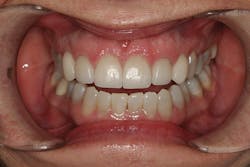

A 32-year-old white female presented for a cosmetic consultation. The patient reported that during her teenage years she had received orthodontic treatment to move her permanent maxillary canines mesially into the spaces that should have been occupied by her congenitally missing lateral incisors. She stated that her dentist, orthodontist, and oral surgeon had decided to place endosseous implants in the canine spaces due to the greater availability of bone in comparison to the bone available in the lateral positions (figure 1). As she grew older, she had become increasingly dissatisfied with the appearance of her smile and was seeking a more updated and esthetic solution (figure 2).

Figure 1

Figure 2

A comprehensive cosmetic, radiographic, and functional evaluation was performed.1 The patient was able to identify the major concerns leading to her dissatisfaction with her smile, including the presence of multiple diastemata, tooth proportion improprieties, unnatural emergence profile of her implant restorations, and her desire for a whiter smile (figure 3).2

Figure 3